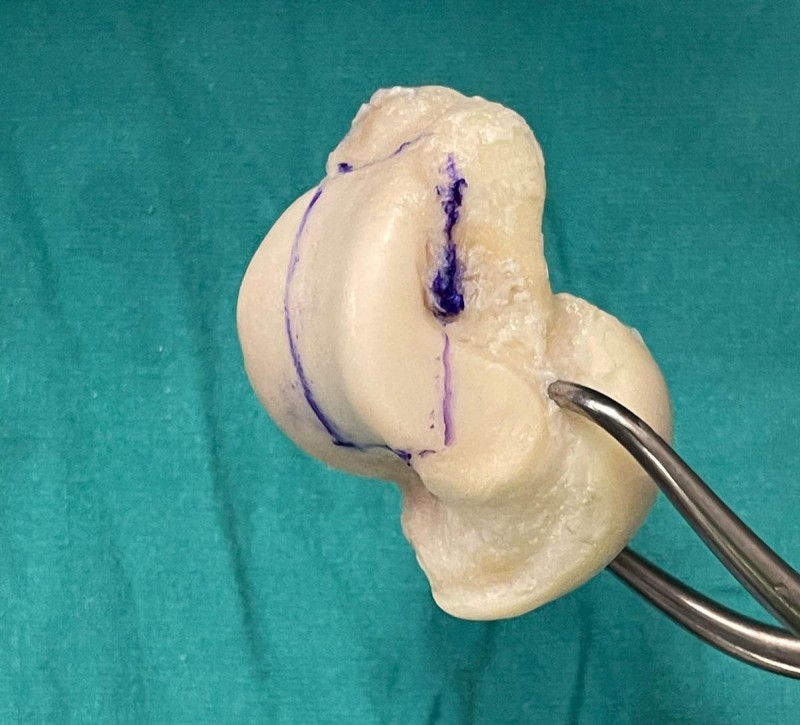

Hastanede yapılan, “Balıkesir’de ilk” nitelikli işlemlerin bir yenisi de Ortopedi ve Travmatoloji Anabilim Dalı Öğretim Üyesi Doç. Dr. Aziz Atik tarafından gerçekleştirildi. Gerçekleştirilen ameliyatla ilgili bilgiler veren Ortopedi ve Travmatoloji Anabilim Dalı Öğretim Üyesi Doç. Dr. Aziz Atik; “Lenf kanseri olan 21 yaşındaki hastamız lenf kanseri tedavisi görerek sağlığına kavuşmuş ancak ilerleyen zamanlarda aldığı tedavilerin yan etkisi olarak ayak bileği kemiğinde çürüme meydana gelmiş. Bize başvuran hastamızın eklem yüzeyi bozulmuş ve hastamız yürümekte zorlanıyor, topallıyordu. Büyük bir lezyonu olan hastamıza büyük lezyonlarda uygulanan en iyi tedavi yöntemi olan ve nadir olarak yapılan bir ameliyatla kadavra donörden kemik ve kıkırdak doku nakli gerçekleştirdik.” ifadelini kullandı. Ülkemizde kemik ve kıkırdak bankası olmadığının altını çizen Doç. Dr. Aziz Atik, yurt dışından bir donör bulmak için çalışmalar yaptıklarını ve yurtdışından kemik bulunduğunda ivedi bir şekilde ameliyatı gerçekleştirdiklerini söyledi. Ameliyatın son derece başarılı geçtiğini belirten Doç. Dr. Aziz Atik, güzel bir eklem düzeyi elde ettiklerini ve ameliyatla genç bir insanın topallamadan, ağrısız yürümesini hedeflendiklerini dile getirdi.